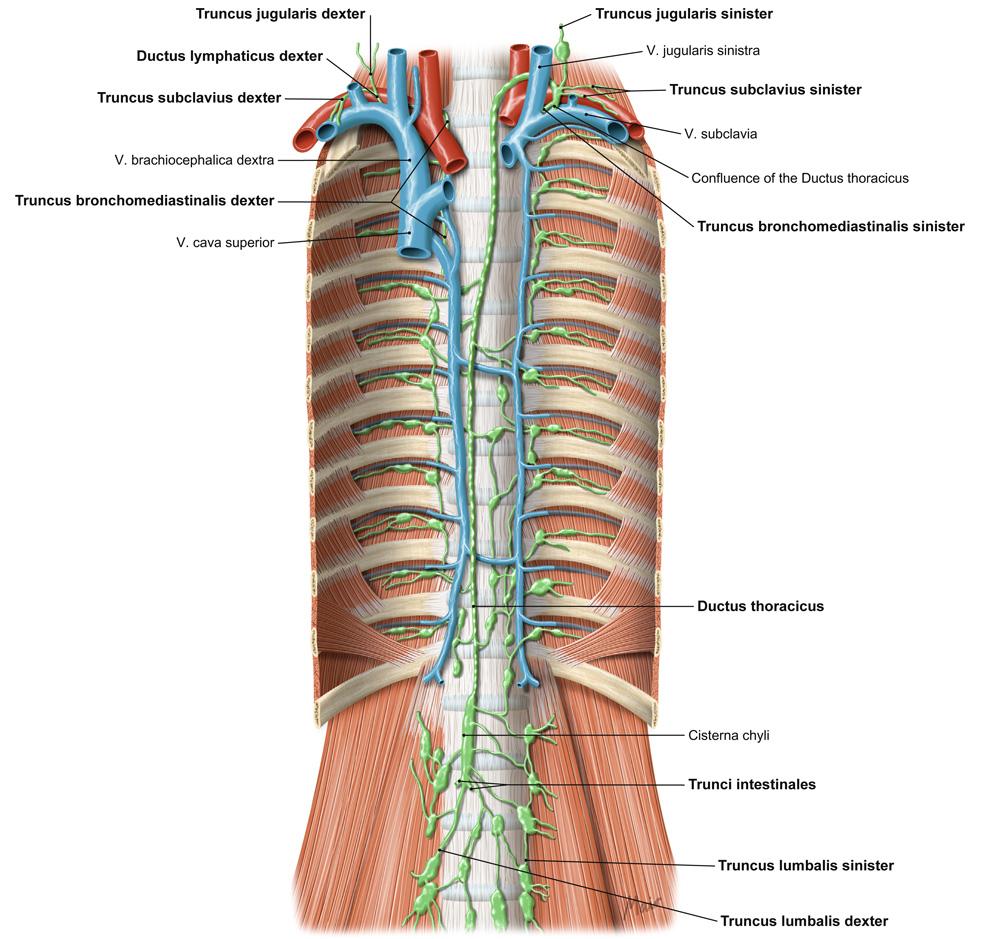

Fig 3.39: Lymfewegen

-

arcus aortae

v brachiocephalica sinistra = v anonyma v subclavia dextra v jugularis interna dextra v jugularis interna sinistra v subclavia sinistra -

ductus thoracicus (groen)

truncus jugularis sinister truncus subclavius sinister truncus jugularis dexter truncus subclavius dexter ductus lymphaticus dexter

Sobotta: Fig 5.25